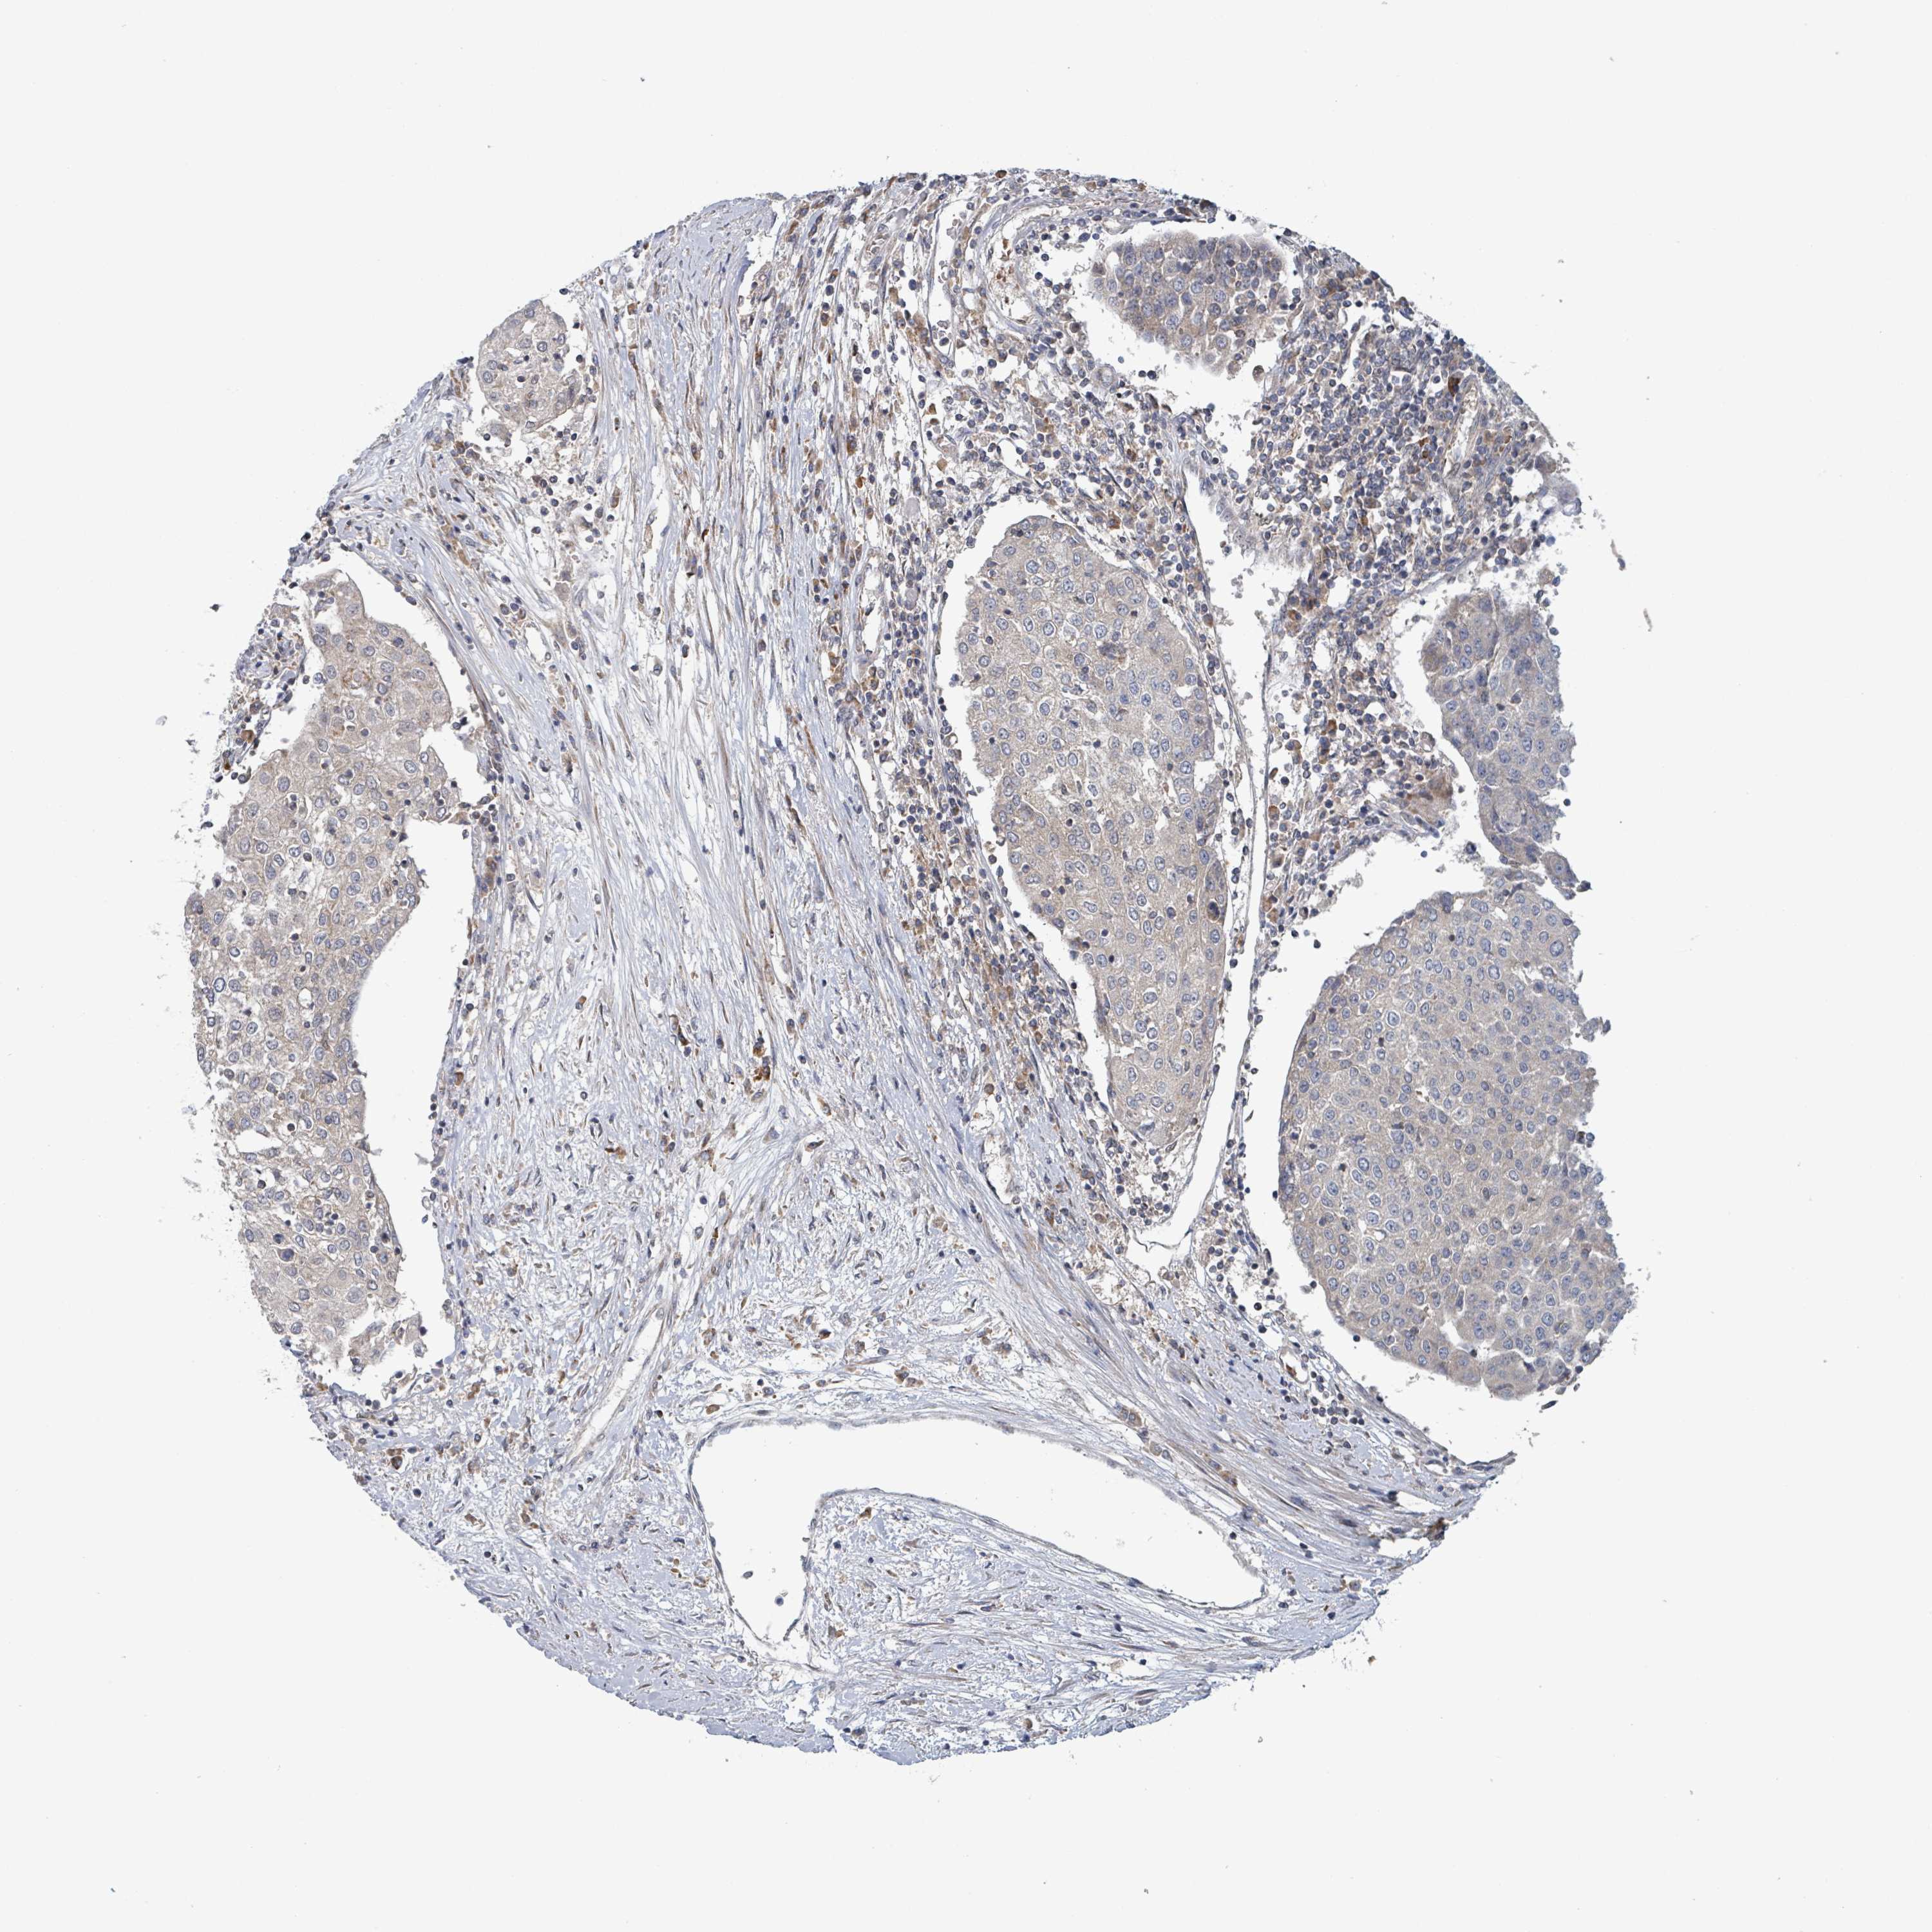

UROTHELIAL CANCER - Protein expressioni

A mouse-over function shows sample information and annotation data. Click on an image to view it in a full screen mode. Samples can be filtered based on level of antibody staining by selecting one or several of the following categories: high, medium, low and not detected. The assay and annotation is described here.

Note that samples used for immunohistochemistry by the Human Protein Atlas do not correspond to samples in the TCGA dataset.

Antibody stainingi

Antibody staining in the annotated cell types in the current human tissue is reported as not detected, low, medium, or high, based on conventional immunohistochemistry profiling in selected tissues. This score is based on the combination of the staining intensity and fraction of stained cells.

Each image is clickable and will lead to virtual microscopy that enables deeper exploration of all samples and also displays staining intensity scores, fraction scores and subcellular localization as well as patient and tissue information for each sample.

Antibody HPA050724

Staining

High

Medium

Low

Not detected

Intensity

Strong

Moderate

Weak

Negative

Quantity

>75%

75%-25%

<25%

None

Location

Nuclear

Cytoplasmic/membranous

Cytoplasmic/membranous,nuclear

Urothelial carcinoma, High grade

Urothelial carcinoma, Low grade